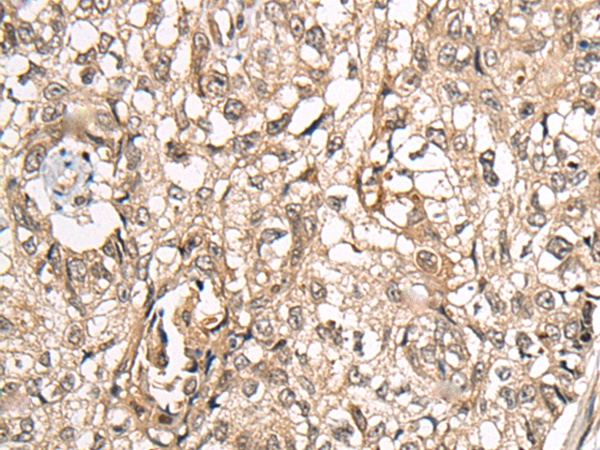

IHC positive control: |

Human liver cancer and human lung cancer |

IHC Recommend dilution: |

20-100 |